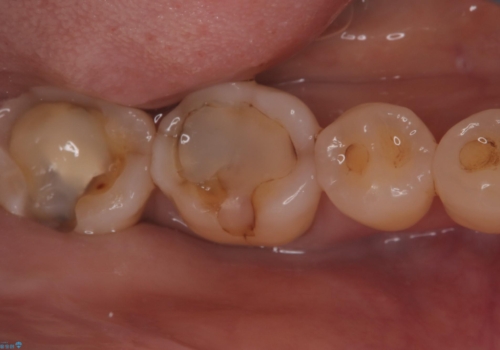

- 主訴:プラスチックの劣化が気になる。

咬合面にCR(コンポジットレジン)修復が広範囲にされており、劣化のしにくさや審美性からセラミックインレーでのやり替えとなりました。

今回残存歯質量から破折のリスクを説明し、クラウンでのやり替えも提案しましたが歯質切削量が多くなることから一度インレーで様子を見ることとなりました。